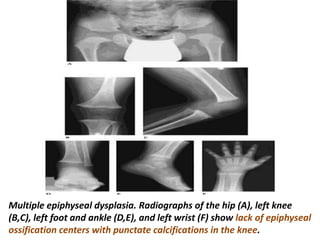

Multiple epiphyseal dysplasia. Radiographs of the hip (A), left knee

(B,C), left foot and ankle (D,E), and left wrist (F) show lack of epiphyseal

ossification centers with punctate calcifications in the knee.